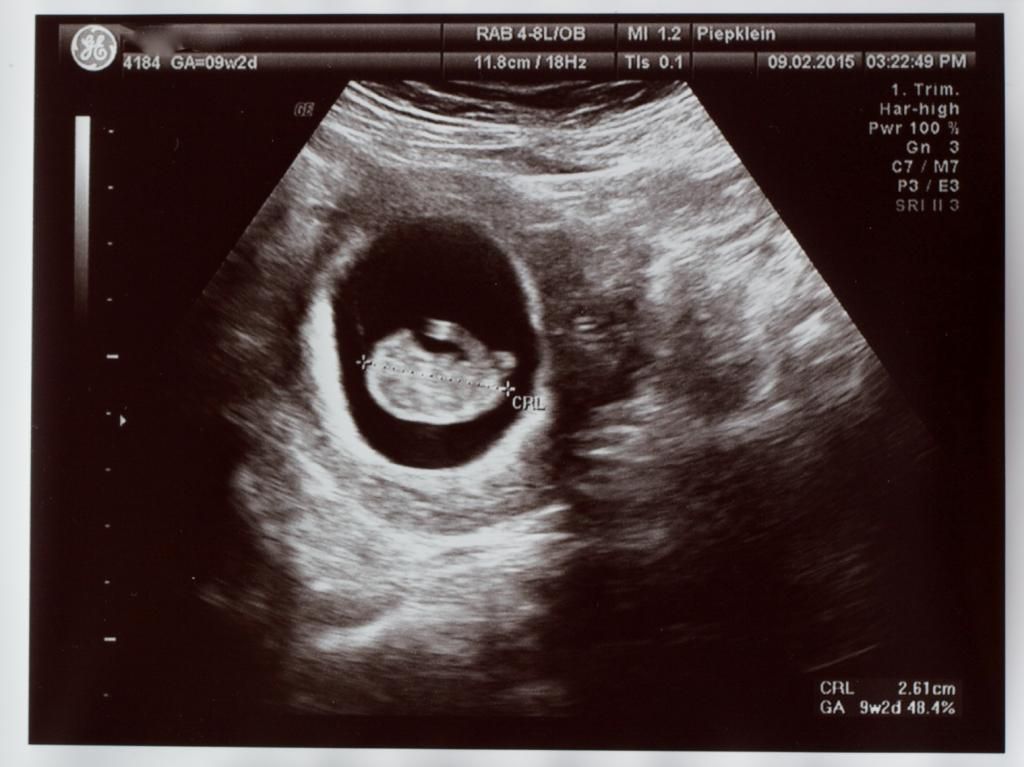

Wizzymaandag 23 februari 2015 @ 21:33

Vandaag voor de 2x een termijnecho gehad. De echoscopist was niet zeker van zijn zaak. Mijn baarmoeder is naar achteren gekanteld. Maar alle echo's lieten dezelfde termijn zien. Mijn uitgerekende datum mag naar 12-09-2015.

Nog gevraagd naar de nub-theorie maar dat vond hij maar een bakerpraatje -O- . Misschien kunnen jullie er wat uithalen. Al ligt hij/zij er niet goed voor.

Bij 9 weken

SPOILER

IMG_1172_zpsubeajnp8.jpg

IMG_1171_zpsqdkfjrn1.jpg

Bij 11 weken

IMG_1168_zps3f8bmibm.jpg

IMG_1166_zpsikkamaet.jpg

Tussendoor nog te horen gekregen dat de nekplooi niet verdikt is ^O^

Is nog iets te vroeg om de NUB vast te stellen, dat is tussen 12 en 14 weken. De NUB kan nog iets veranderen namelijk. Maar voor nu neig ik naar een jongen.

op beide foto's is geen nub te zien :) maar zoals eerder gezegd is het ook nog te vroeg voor nub. Overigens is nub gewoon wetenschappelijk bewezen, en zeker geen bakerpraatje. Alleen het is geen theorie die 100% zekerheid geeft over het geslacht.